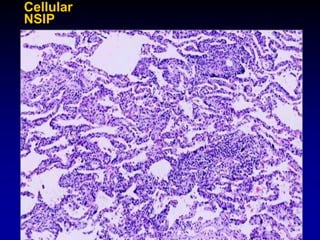

Nonspecific Interstitial Pneumonia (NSIP)

Pattern

• Preserved architecture,

variable fibrosis and

cellularity

• Few fibroblastic foci

• Temporally homogenous

• Inconsistent distribution

Cellular

NSIP